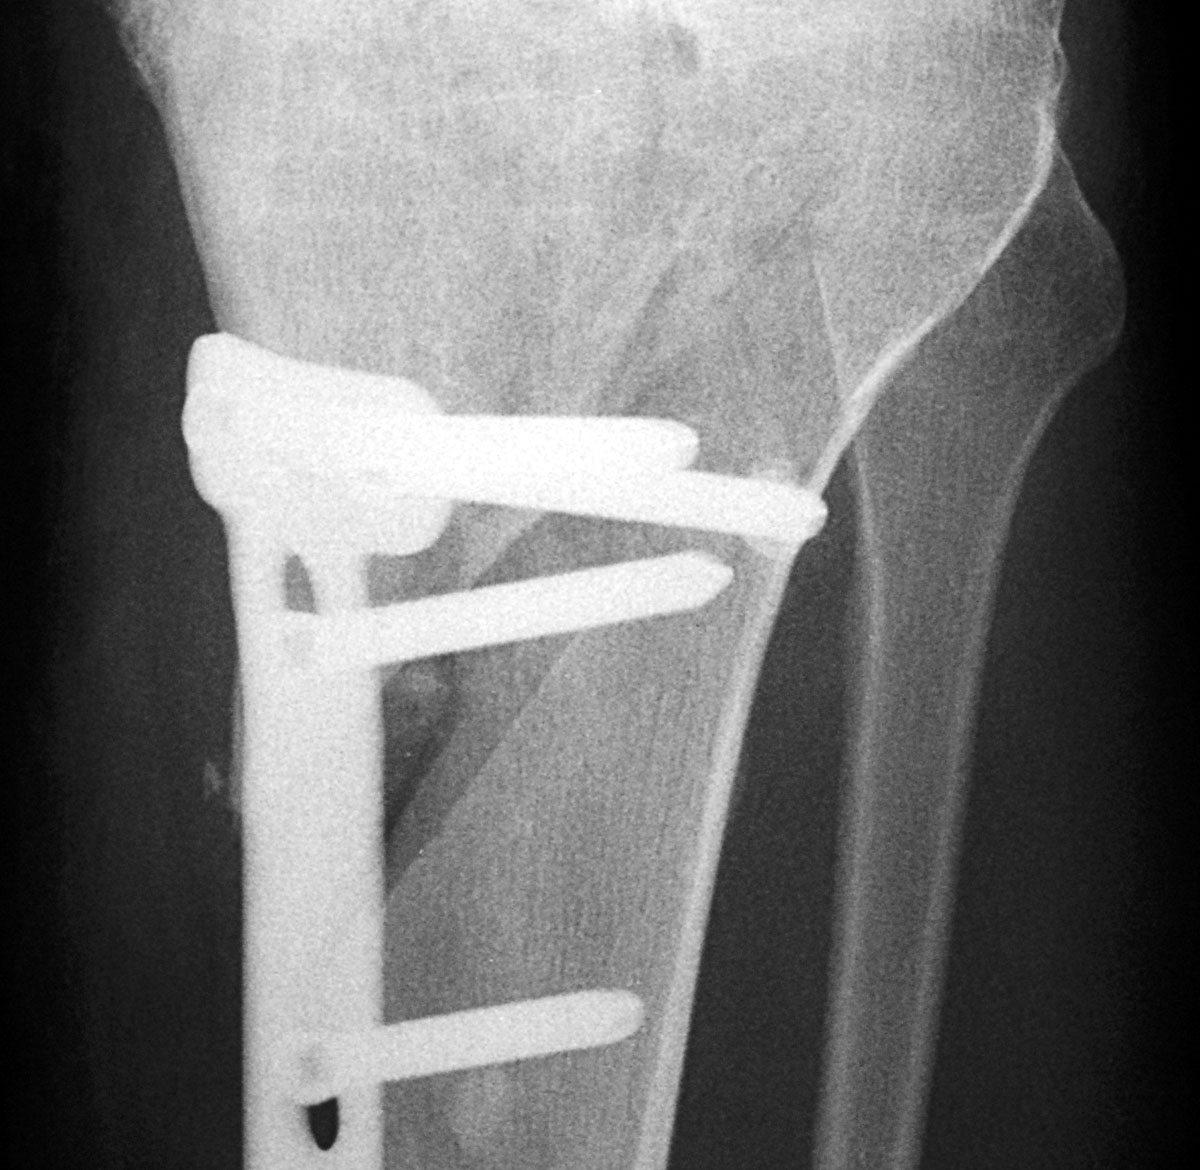

Röntgenbilder Salemspital Bern, 12. August 2005